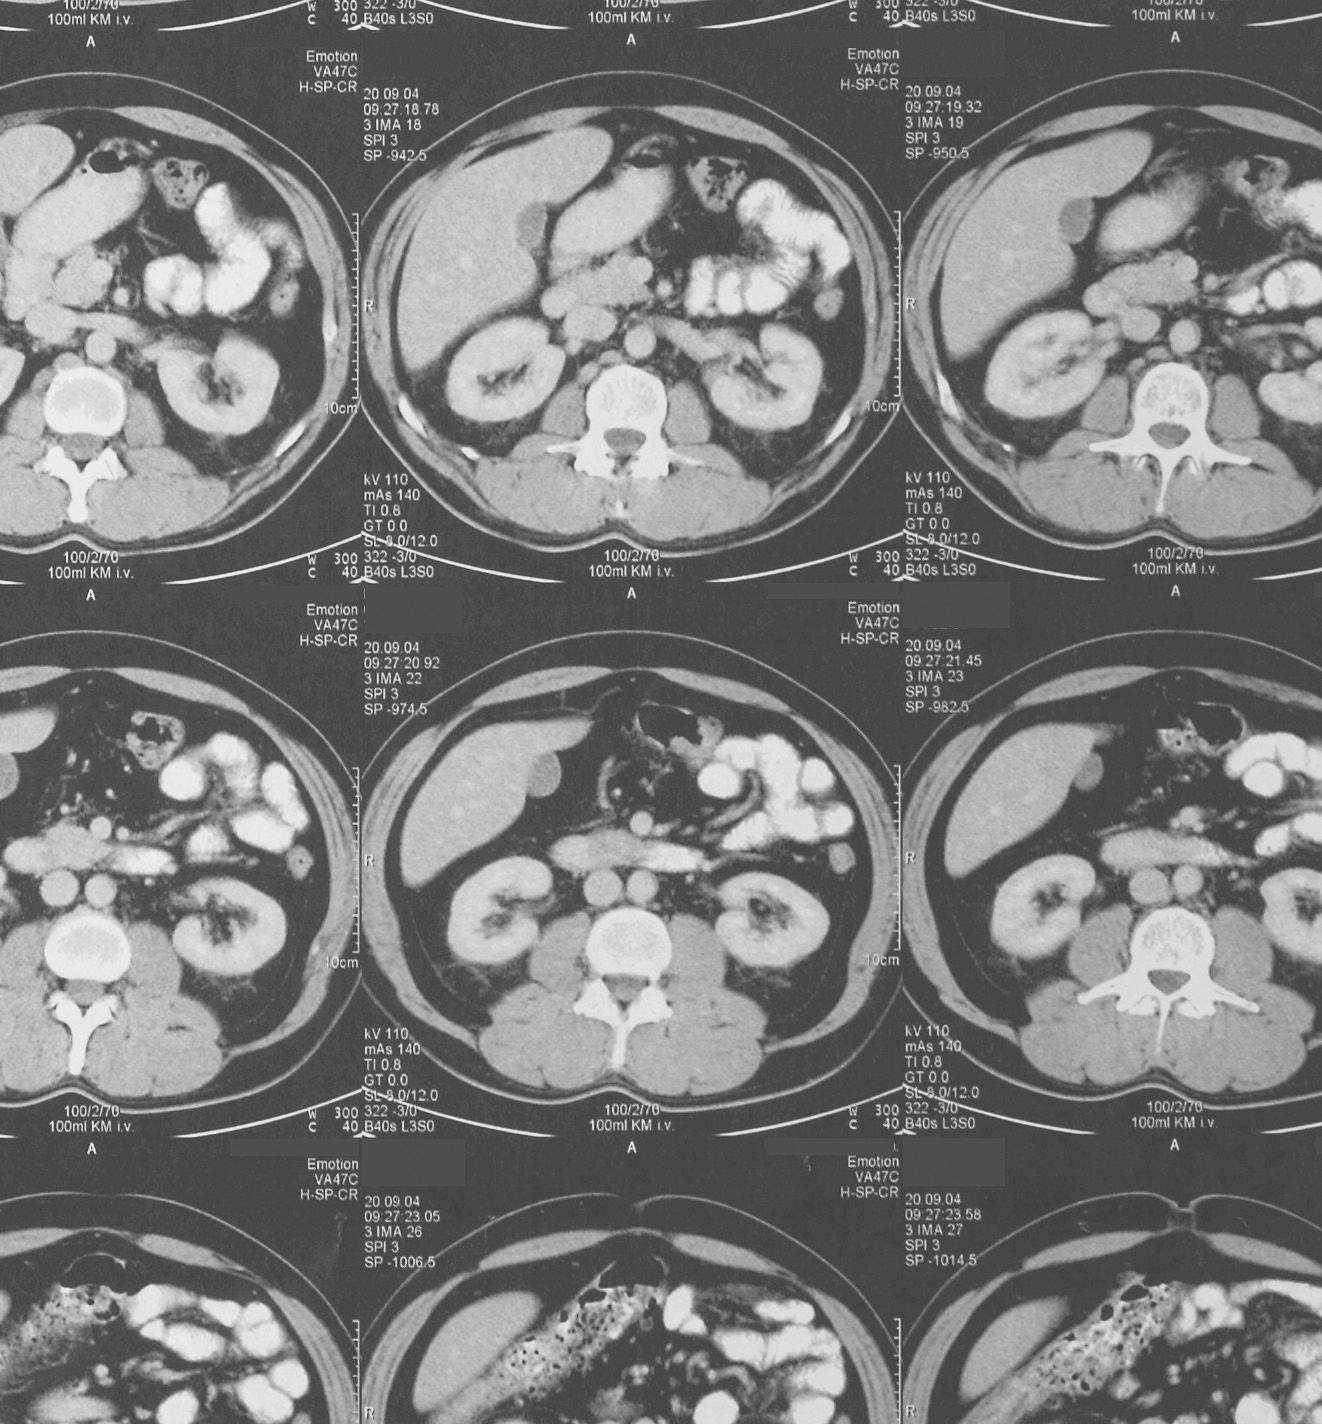

• Diagnostic imaging at up to 60% less than hospital imaging

• In-network with 99% of health insurance plans in Colorado

• Fast prior authorizations assistance for easy scheduling

• same day/next day appointments with extended and weekend hours

• subspecialized radiologists available for consultation

• Prompt standard reports delivered within hours

• Obtain reports quickly through easy-to-access physician portal

• 97% patient satisfaction rate

Refer your patients to our 11 convenient locations throughout metro Denver